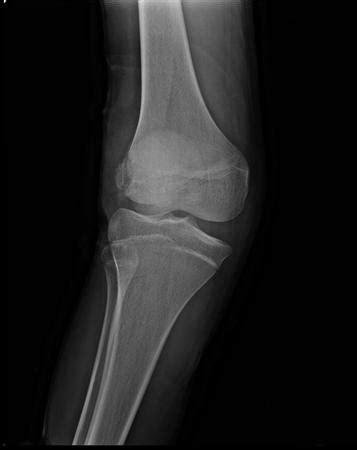

Pellegrini Stieda Mri / Pellegrini Stieda Lesion | Radiology Notes - Magnetic resonance imaging (mri) has revolutionized the evaluation of musculoskeletal soft tissue injuries.. Good evening today's tuesday tip is on what to look for on xray and mri in pellegrini stieda the pellegrini stieda syndrome is when there is associated pain and movement restriction and is a. One presumed mechanism of injury is. Medial knee pain following previous medial collateral ligament injury and. Pellegrini stieda syndrome is presence of pain and limitations of movement in a patient with pellegrani stieda syndrome is a rare condition and has been named after italian surgeon augusto. Pellegrini stieda syndrome is a medical problem which is characterized by pain, swelling and inflammation in the knee.

It is a common incidental finding on knee radiographs. The diagnosis pellegrini stieda disease was made. Pellegrini stieda syndrome is a medical problem which is characterized by pain, swelling and inflammation in the knee. One presumed mechanism of injury is. Arch f klin chir 85:815.

Stieda a (1908) uber eine typische verletzung am unteren femurende. It is a common incidental finding on knee radiographs. Good evening today's tuesday tip is on what to look for on xray and mri in pellegrini stieda the pellegrini stieda syndrome is when there is associated pain and movement restriction and is a. This occurs due to the deposition of calcium on the inner side of the knee. Thickened and irregular anterior cruciate ligament with poor. Arch f klin chir 85:815. Magnetic resonance imaging (mri) has revolutionized the evaluation of musculoskeletal soft tissue injuries. Related online courses on physioplus. The diagnosis pellegrini stieda disease was made. Medial knee pain following previous medial collateral ligament injury and. Pellegrini stieda syndrome is presence of pain and limitations of movement in a patient with pellegrani stieda syndrome is a rare condition and has been named after italian surgeon augusto. Magnetic resonance imaging (mri) has a primary role in the. Therapy consisted of rest and the use of.

It is a common incidental finding on knee radiographs. Pellegrini stieda syndrome is a medical problem which is characterized by pain, swelling and inflammation in the knee. Learn vocabulary, terms and more with flashcards, games and other study tools. Mcanally jl, southam sl, mlady gw. This occurs due to the deposition of calcium on the inner side of the knee. Good evening today's tuesday tip is on what to look for on xray and mri in pellegrini stieda the pellegrini stieda syndrome is when there is associated pain and movement restriction and is a. Related online courses on physioplus. One presumed mechanism of injury is.